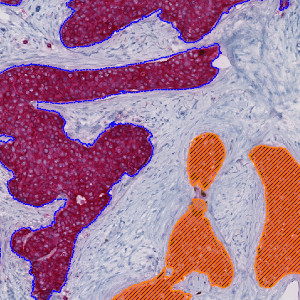

Image of a slide physically double stained with p63 (brown chromogen) and CK7/19 (red chromogen). Notice how only some structures display p63 positive nuclei.

The Invasive Tumor Detection APP is based on a physical double stain of p63+CK7/19. Invasive tumor components are identified as regions positive for CK, whereas non-invasive tumor components are identified as regions positive for both CK and p63, and are excluded.